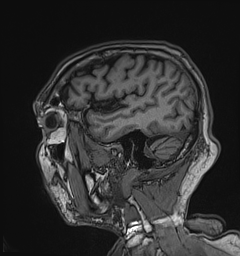

I stopped and steadied myself, determined to get my body under control. Yet, no matter how slowly and deliberately my brain tried to steer me in one direction, my body insisted on going in another. Maybe that ‘pop’ I felt in the center of my skull really was a stroke.

My neurologist said I was lucky the stroke occurred in a part of the brain that did not affect thinking or speech. (Insert joke here!)